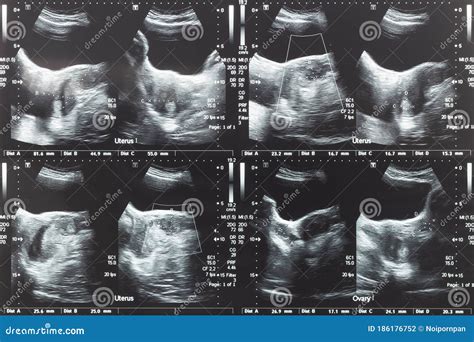

Uterus Test Videos often delve into these conditions, explaining their symptoms, causes, and diagnostic methods. For instance, a video might show how a transvaginal ultrasound is used to detect uterine fibroids or how a biopsy is performed to diagnose uterine cancer.

• Ultrasound: Uses sound waves to create images of the uterus and surrounding structures.